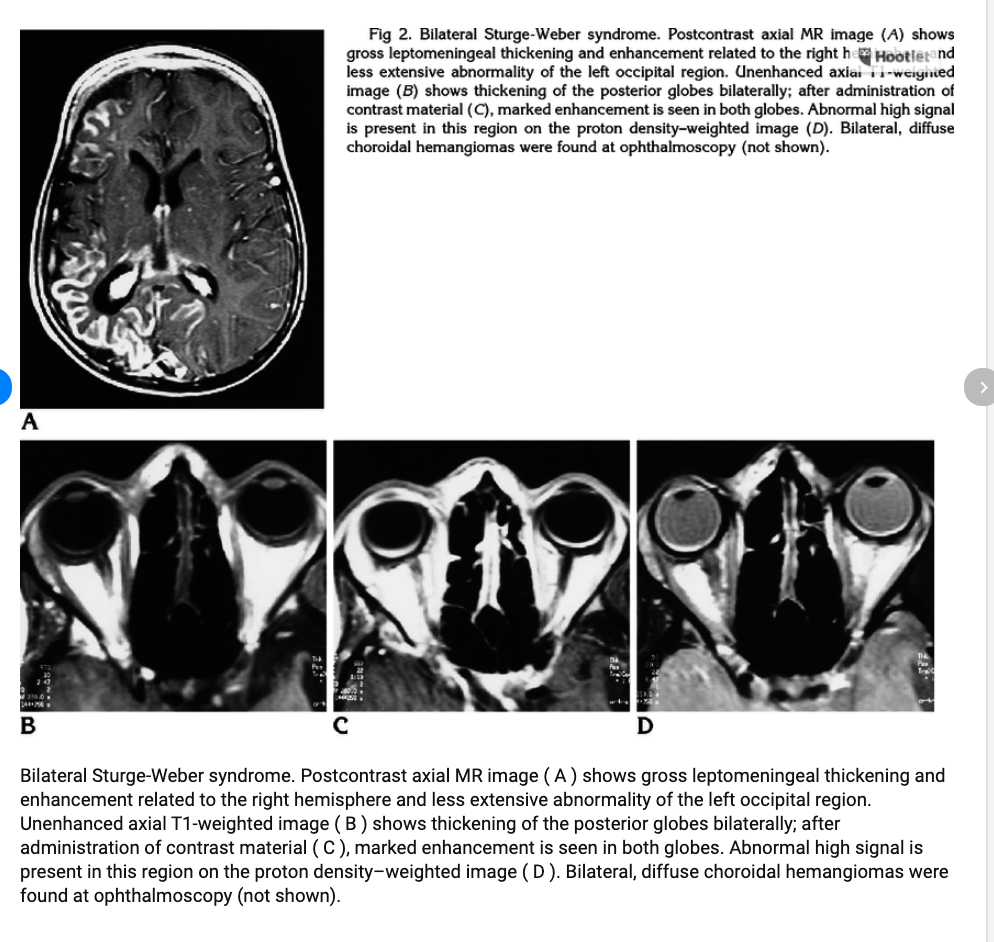

Bilateral Sturge-Weber syndrome. Postcontrast axial MR image ( A ) shows gross leptomeningeal thickening and enhancement related to the right hemisphere and less extensive abnormality of the left occipital region. Unenhanced axial T1-weighted image ( B ) shows thickening of the posterior globes bilaterally; after administration of contrast material ( C ), marked enhancement is seen in both globes. Abnormal high signal is present in this region on the proton density–weighted image ( D ). Bilateral, diffuse choroidal hemangiomas were found at ophthalmoscopy (not shown).